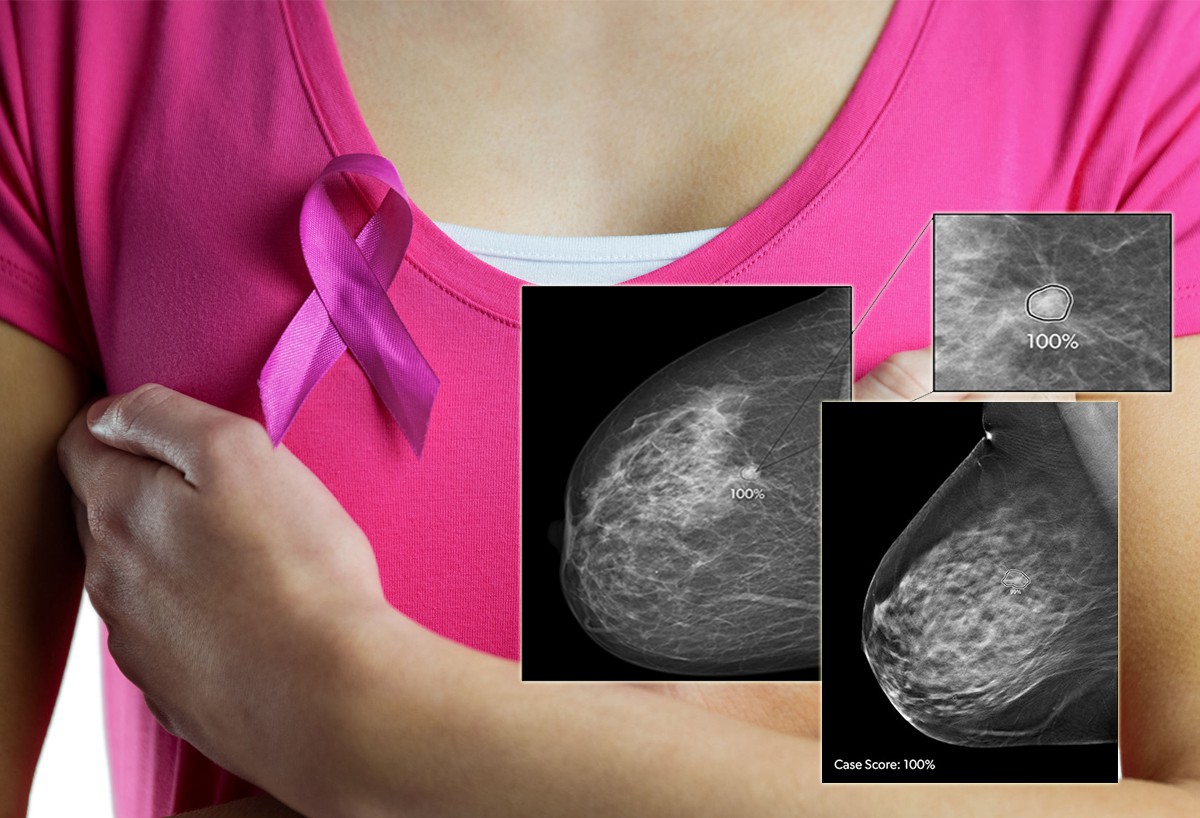

Что такое маммография: важность, процесс и результаты

Раздел: Необычные решения